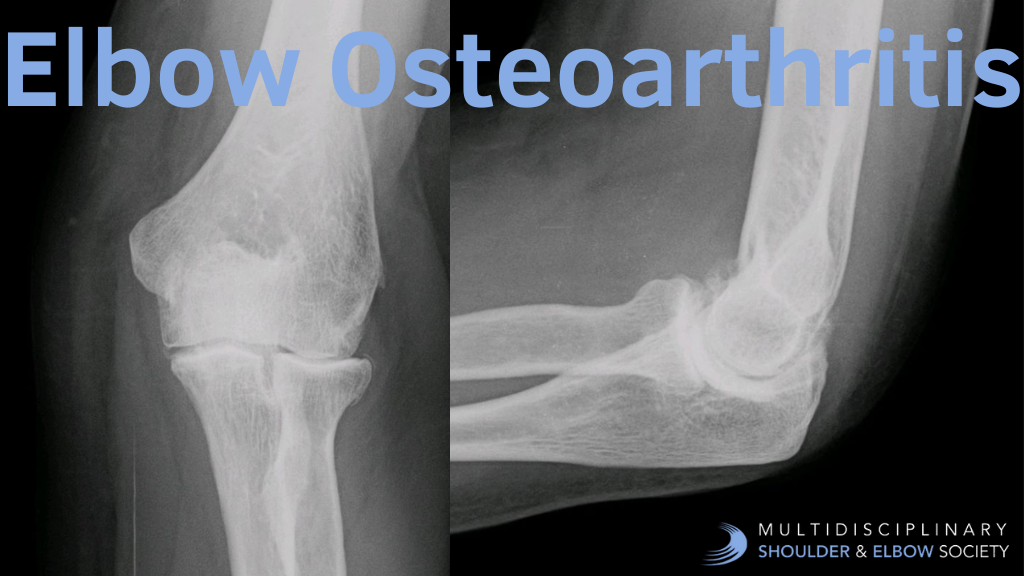

A Guide to Imaging for Elbow Osteoarthritis

A Systematic Guide to Reading Elbow Osteoarthritis Radiographs

Start with standard anteroposterior (AP) and lateral views of the elbow joint. For complex cases, oblique views can provide additional insights.

Joint space narrowing is a key indicator of osteoarthritis, predominantly affecting the radiocapitellar joint (58%) and less commonly the ulnotrochlear joint (16%). Look for characteristic nonuniform narrowing patterns throughout the joint spaces.

Osteophytes, or bony outgrowths, are hallmark features that appear as irregular projections at joint margins. They most commonly develop at the:

- Olecranon (96% of cases)

- Coronoid process (90%)

- Radial head (86%)

- Coronoid and radial fossae (64%)

Subchondral Bone Changes

Examine the bone beneath the cartilage for two key changes:

- Subchondral sclerosis: Areas of increased bone density

- Subchondral cysts: Appearing as radiolucent regions surrounded by sclerotic borders

In progressed cases, expect to find:

- Significant radiocapitellar joint narrowing

- Prominent osteophyte formation on the olecranon and coronoid processes

- Marked subchondral sclerosis at the ulnohumeral joint

- Visible intra-articular loose bodies